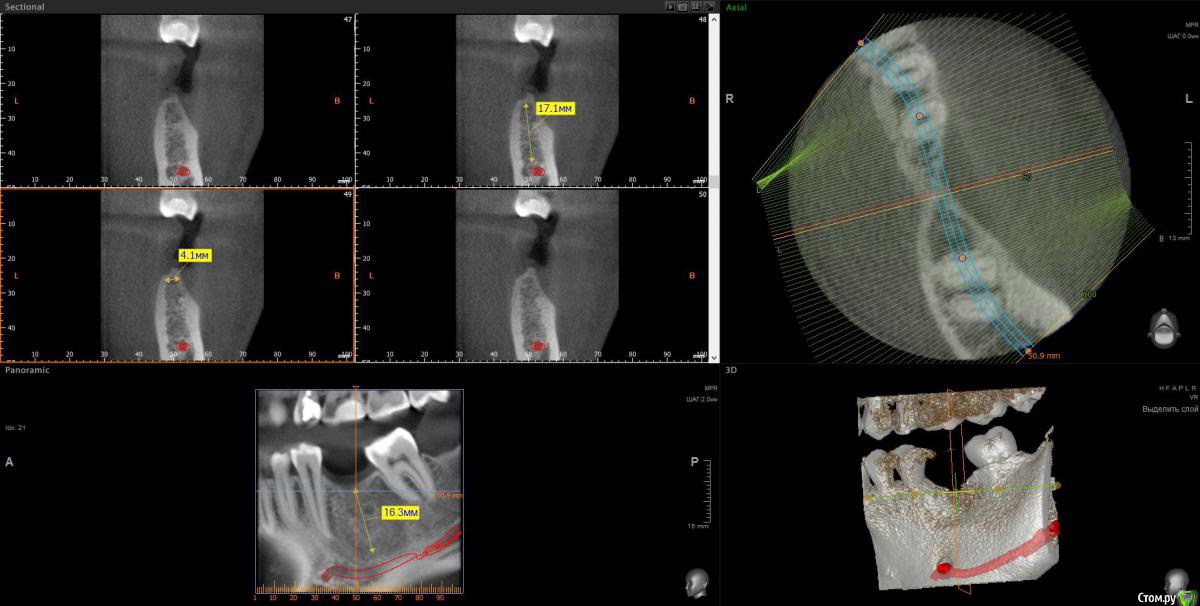

wladdX Опубликовано 1 декабря, 2016 Поделиться Опубликовано 1 декабря, 2016 (изменено) Вот пара скриншотов. Изменено 1 декабря, 2016 пользователем wladdX 1 1 Ссылка на комментарий

Powermen Опубликовано 1 декабря, 2016 Автор Поделиться Опубликовано 1 декабря, 2016 measurement_1.jpgmeasurement_2.jpgВот пара скриншотов.спасибо, что сделал скрины)) Ссылка на комментарий